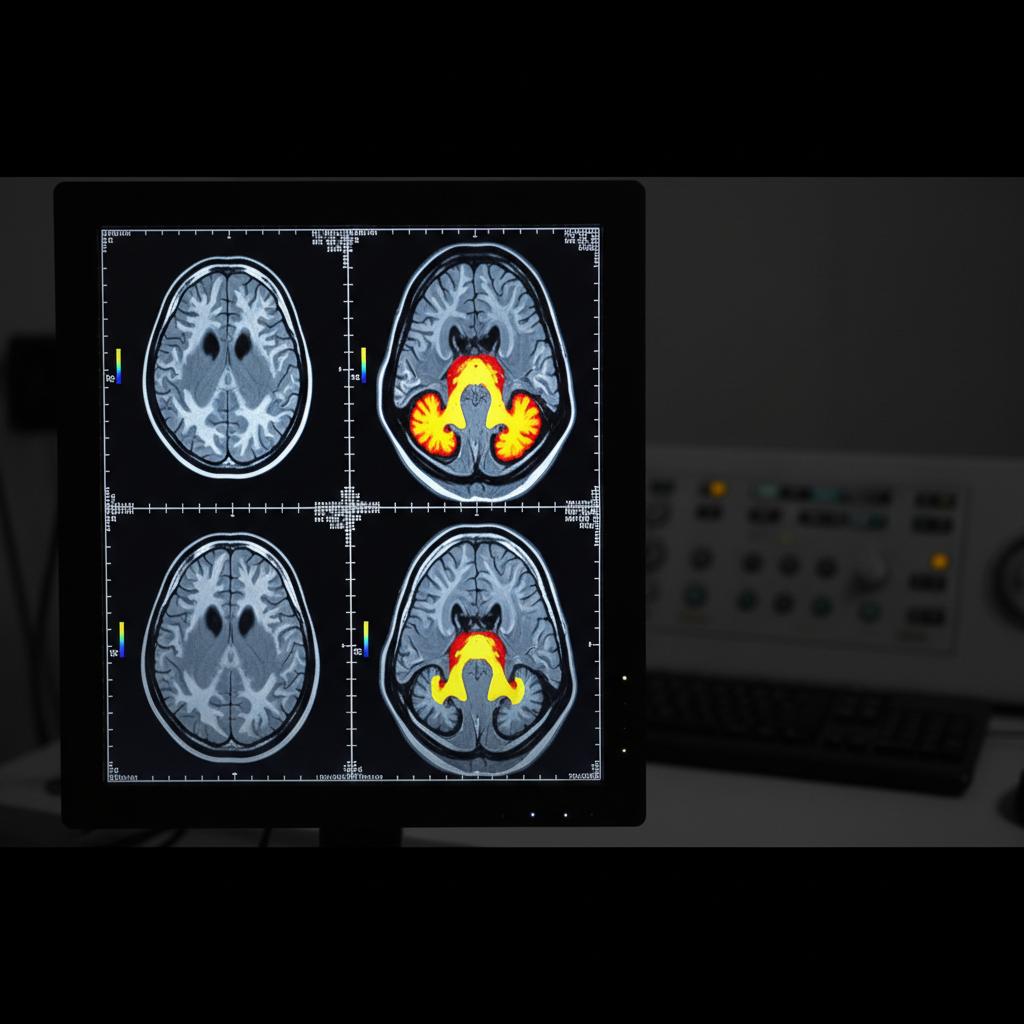

Trauma działa jak wirus w systemie operacyjnym mózgu – niszczy ścieżki neuronalne, blokuje dostęp do wspomnień i prowadzi do powstawania tzw. „czarnych dziur pamięciowych”. Najnowsze badania neuroobrazowe pokazują, że osoby po przeżyciu ciężkiego stresu lub traumy mają zmniejszoną objętość hipokampa – obszaru odpowiedzialnego za konsolidację pamięci (Bremner, 2023). Efekt? Trudności w zapamiętywaniu nowych informacji, déjà vu, nieoczekiwane luki w pamięci, a czasem całkowita amnezja dotycząca traumatycznych wydarzeń.

Równocześnie neuroplastyczność mózgu daje nadzieję – odpowiednia psychoterapia, zwłaszcza EMDR i terapia poznawcza, potrafią przywracać zaburzone funkcje poprzez tworzenie nowych ścieżek neuronalnych.